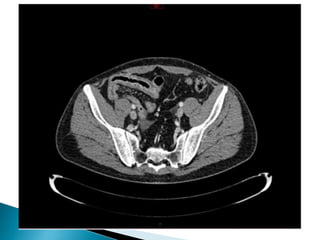

 En 11/2016, douleurs crampoïdes +++

◦ CT-scan abdo : hématome de paroi secondaire à

purpura d’Henoch-Schönlein

 Aspect au CT-Scan :

◦ Epaississement paroi

◦ Engorgement des vsx mésentériques